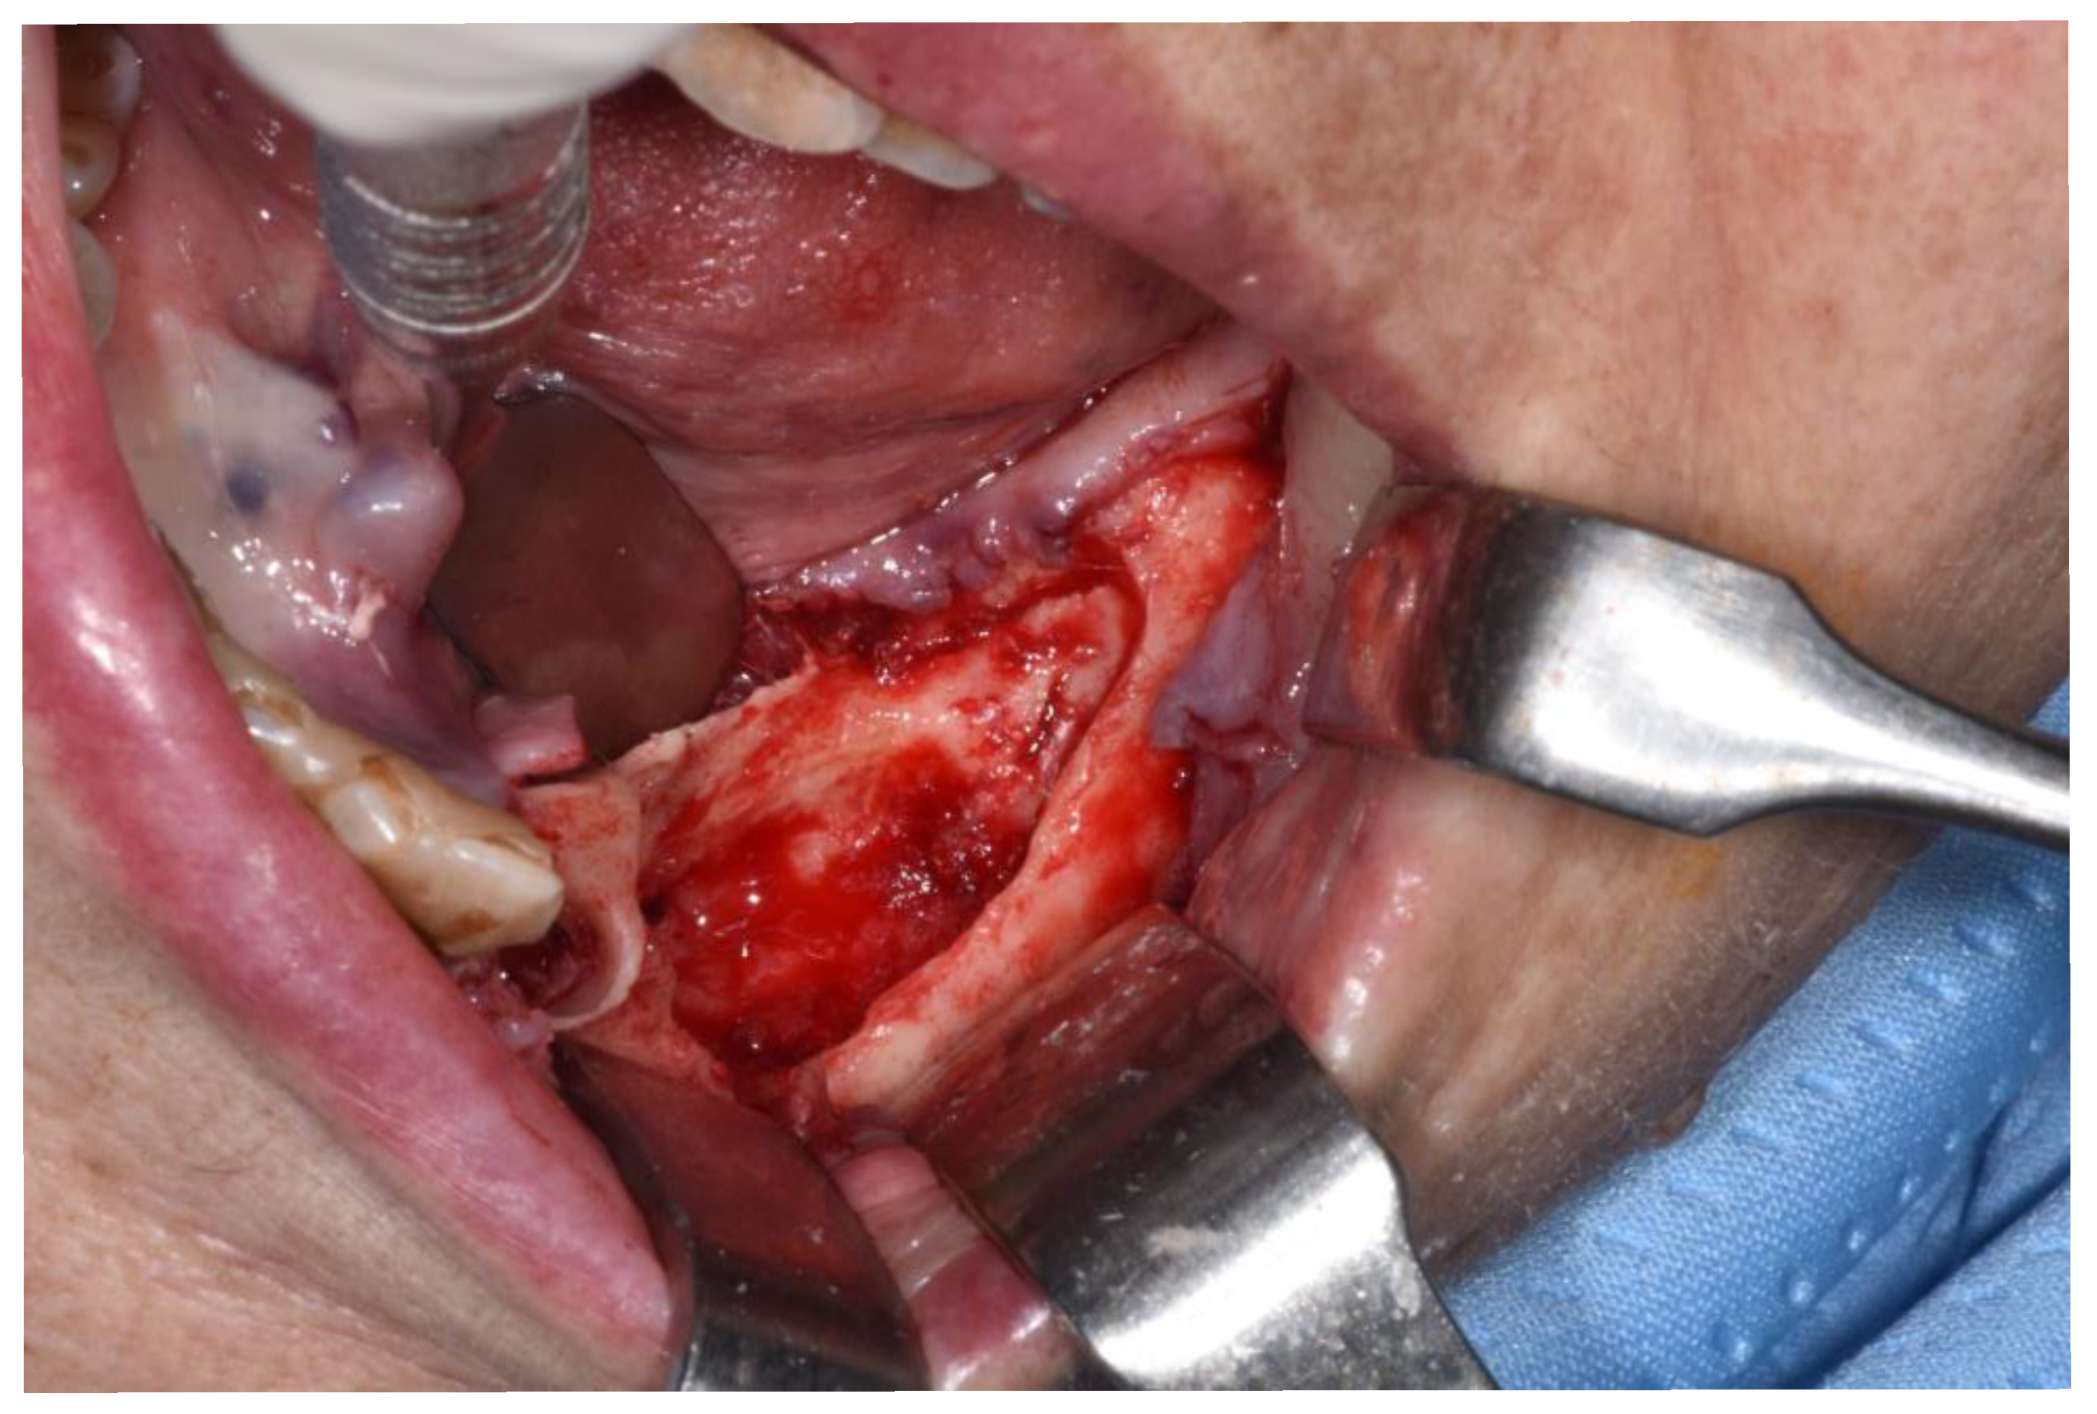

Figure 3.

Clinical appearance when elevating mucoperiosteal flap.

Sub-marginal resection performed using piezoelectric device.

Revision of the cavity until observing bleeding bone.